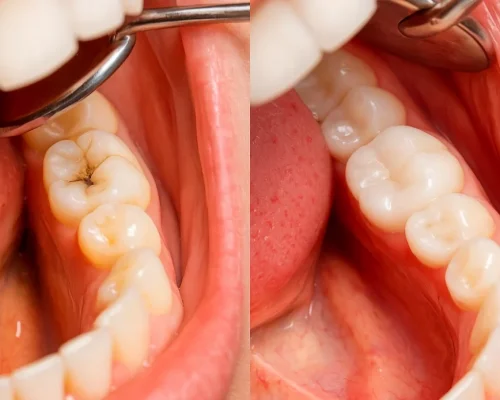

Preventive fillings are used to repair very small cavities or areas of enamel damage before they turn into deep decay. These fillings seal the tooth and prevent further deterioration, helping you avoid more complex procedures like root canals or crowns.

We use tooth-colored composite fillings that blend naturally with your teeth.

Placement of Tooth-Colored Filling Material

Shaping & Polishing for a Natural Finish